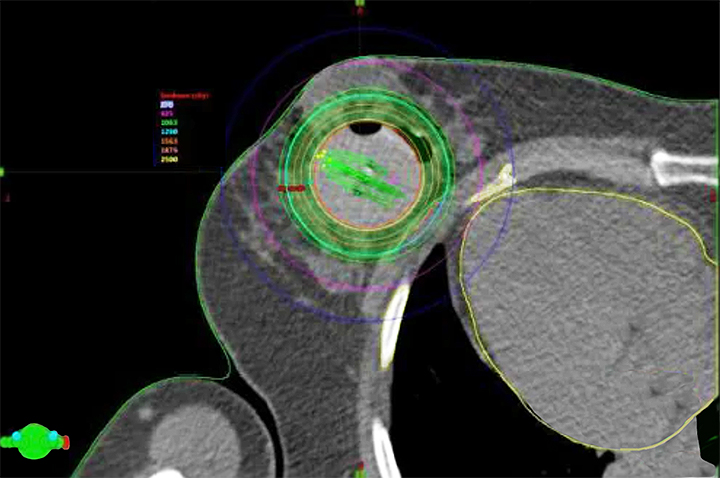

Stereotactic Radiosurgery

Stereotactic Radiosurgery (SRS) delivers a high dose of radiation to small, well-defined tumors in a single dose or in just a few sessions such as with treating pituitary or spine tumors or brain metastasis. The term radiosurgery is derived from this treatment method which has such a dramatic reducing effect on the tumor, that the changes are considered “surgical.” SRS may be used as the primary treatment when a tumor is inaccessible by surgical means or as a boost or adjunct to other treatments for a recurring or malignant tumor.

Low Dose Rate (LDR) brachytherapy is a type of internal radiation therapy where small radioactive seeds or sources are placed inside or near the tumor. These seeds emit radiation at a low dose rate over an extended period, typically several months. The goal is to deliver an ideal dose of radiation directly to the cancer cells while minimizing exposure to surrounding healthy tissues. LDR brachytherapy is commonly used to treat prostate, cervical, endometrial, and skin cancer, as well as brain tumors.